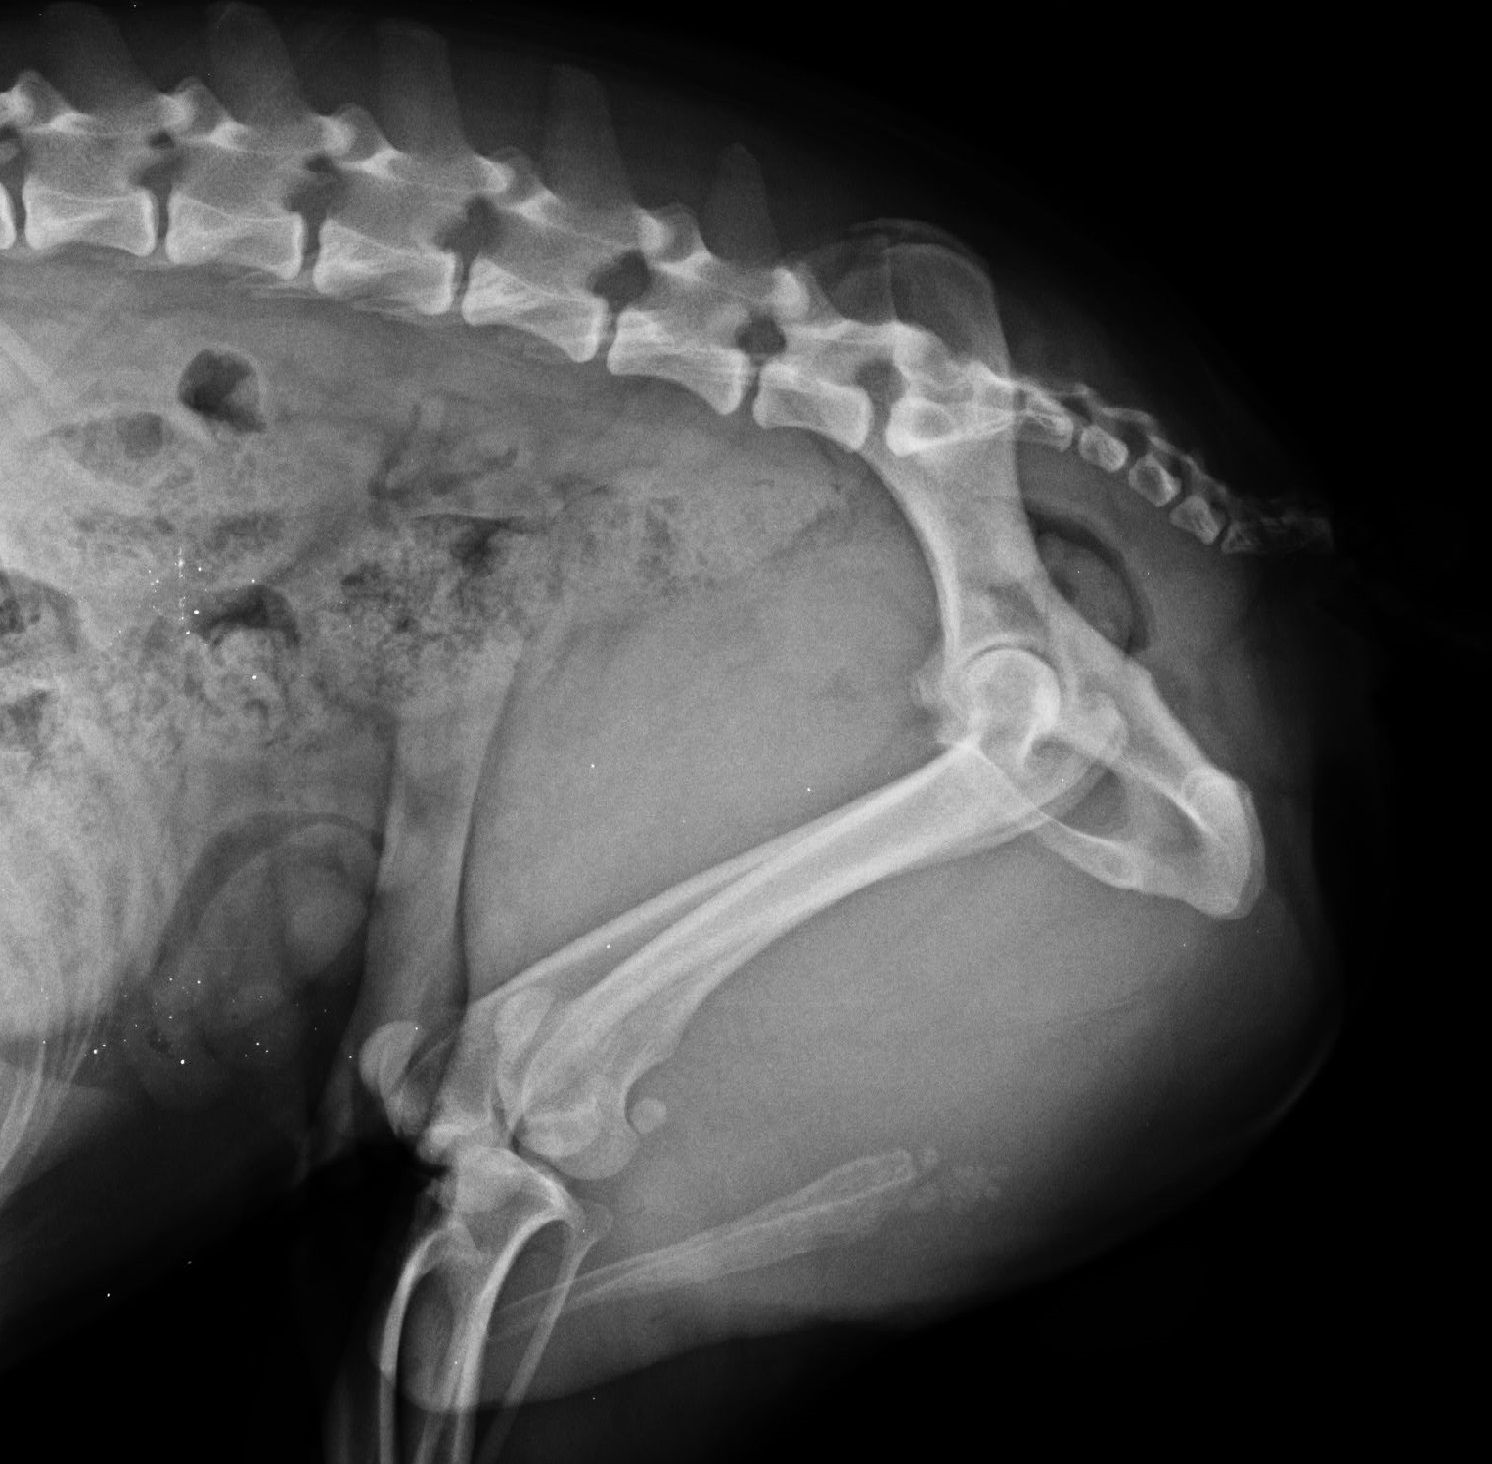

- Radios officielles de dysplasie des hanches ou du coude avec anesthésie